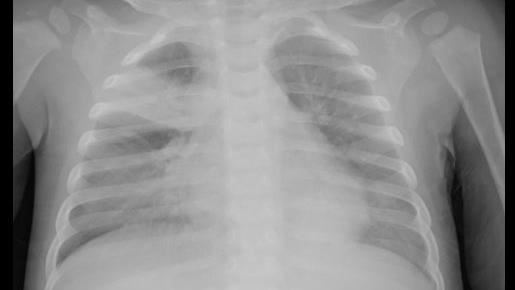

▲X光檢查發現男嬰肺部出現肺炎(圖/童綜合醫院提供)

收治男嬰的童綜合醫院小兒感染科高佳慧醫師表示,男嬰看診並進行相關檢查後,肺部X光發現兩側有肺炎,也發現孩子同時感染呼吸道融合病毒、黴漿菌與肺炎鏈球菌,其中肺炎鏈球菌還感染到血液而導致菌血症,男嬰也因為呼吸衰竭接受插管治療,病童所感染肺炎鏈球菌為高度抗藥性,緊急給予後線抗生素治療,加護病房住院十天後轉普通病房,再住院五天後恢復健康,並開心返家歡度週歲生日,醫護團隊也在男嬰出院當日提前幫他慶生,給予滿滿祝福。